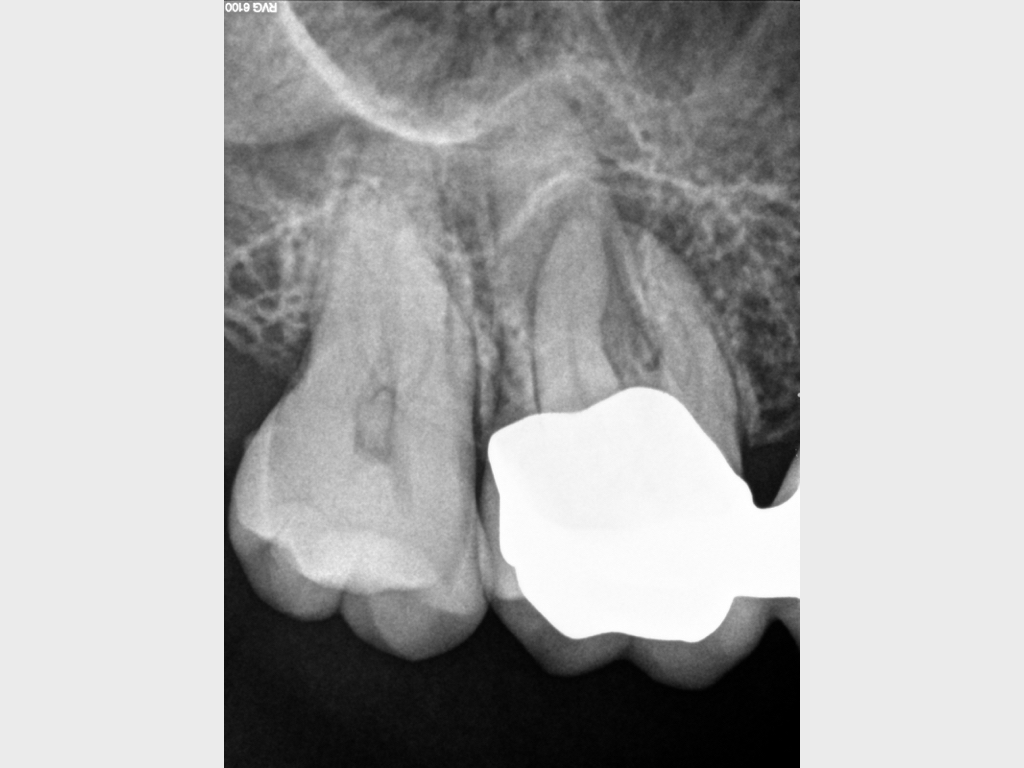

Heilung Express oder Radiodontics